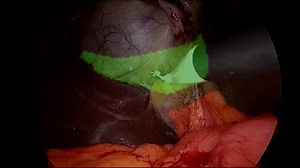

Pain After Gallbladder Surgery - M…

YouTubeMayo Clinic